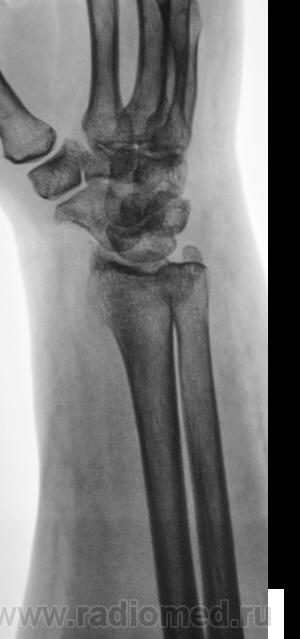

Травма.   Пациент направлен на рентгенографию лучезапястного сустава.